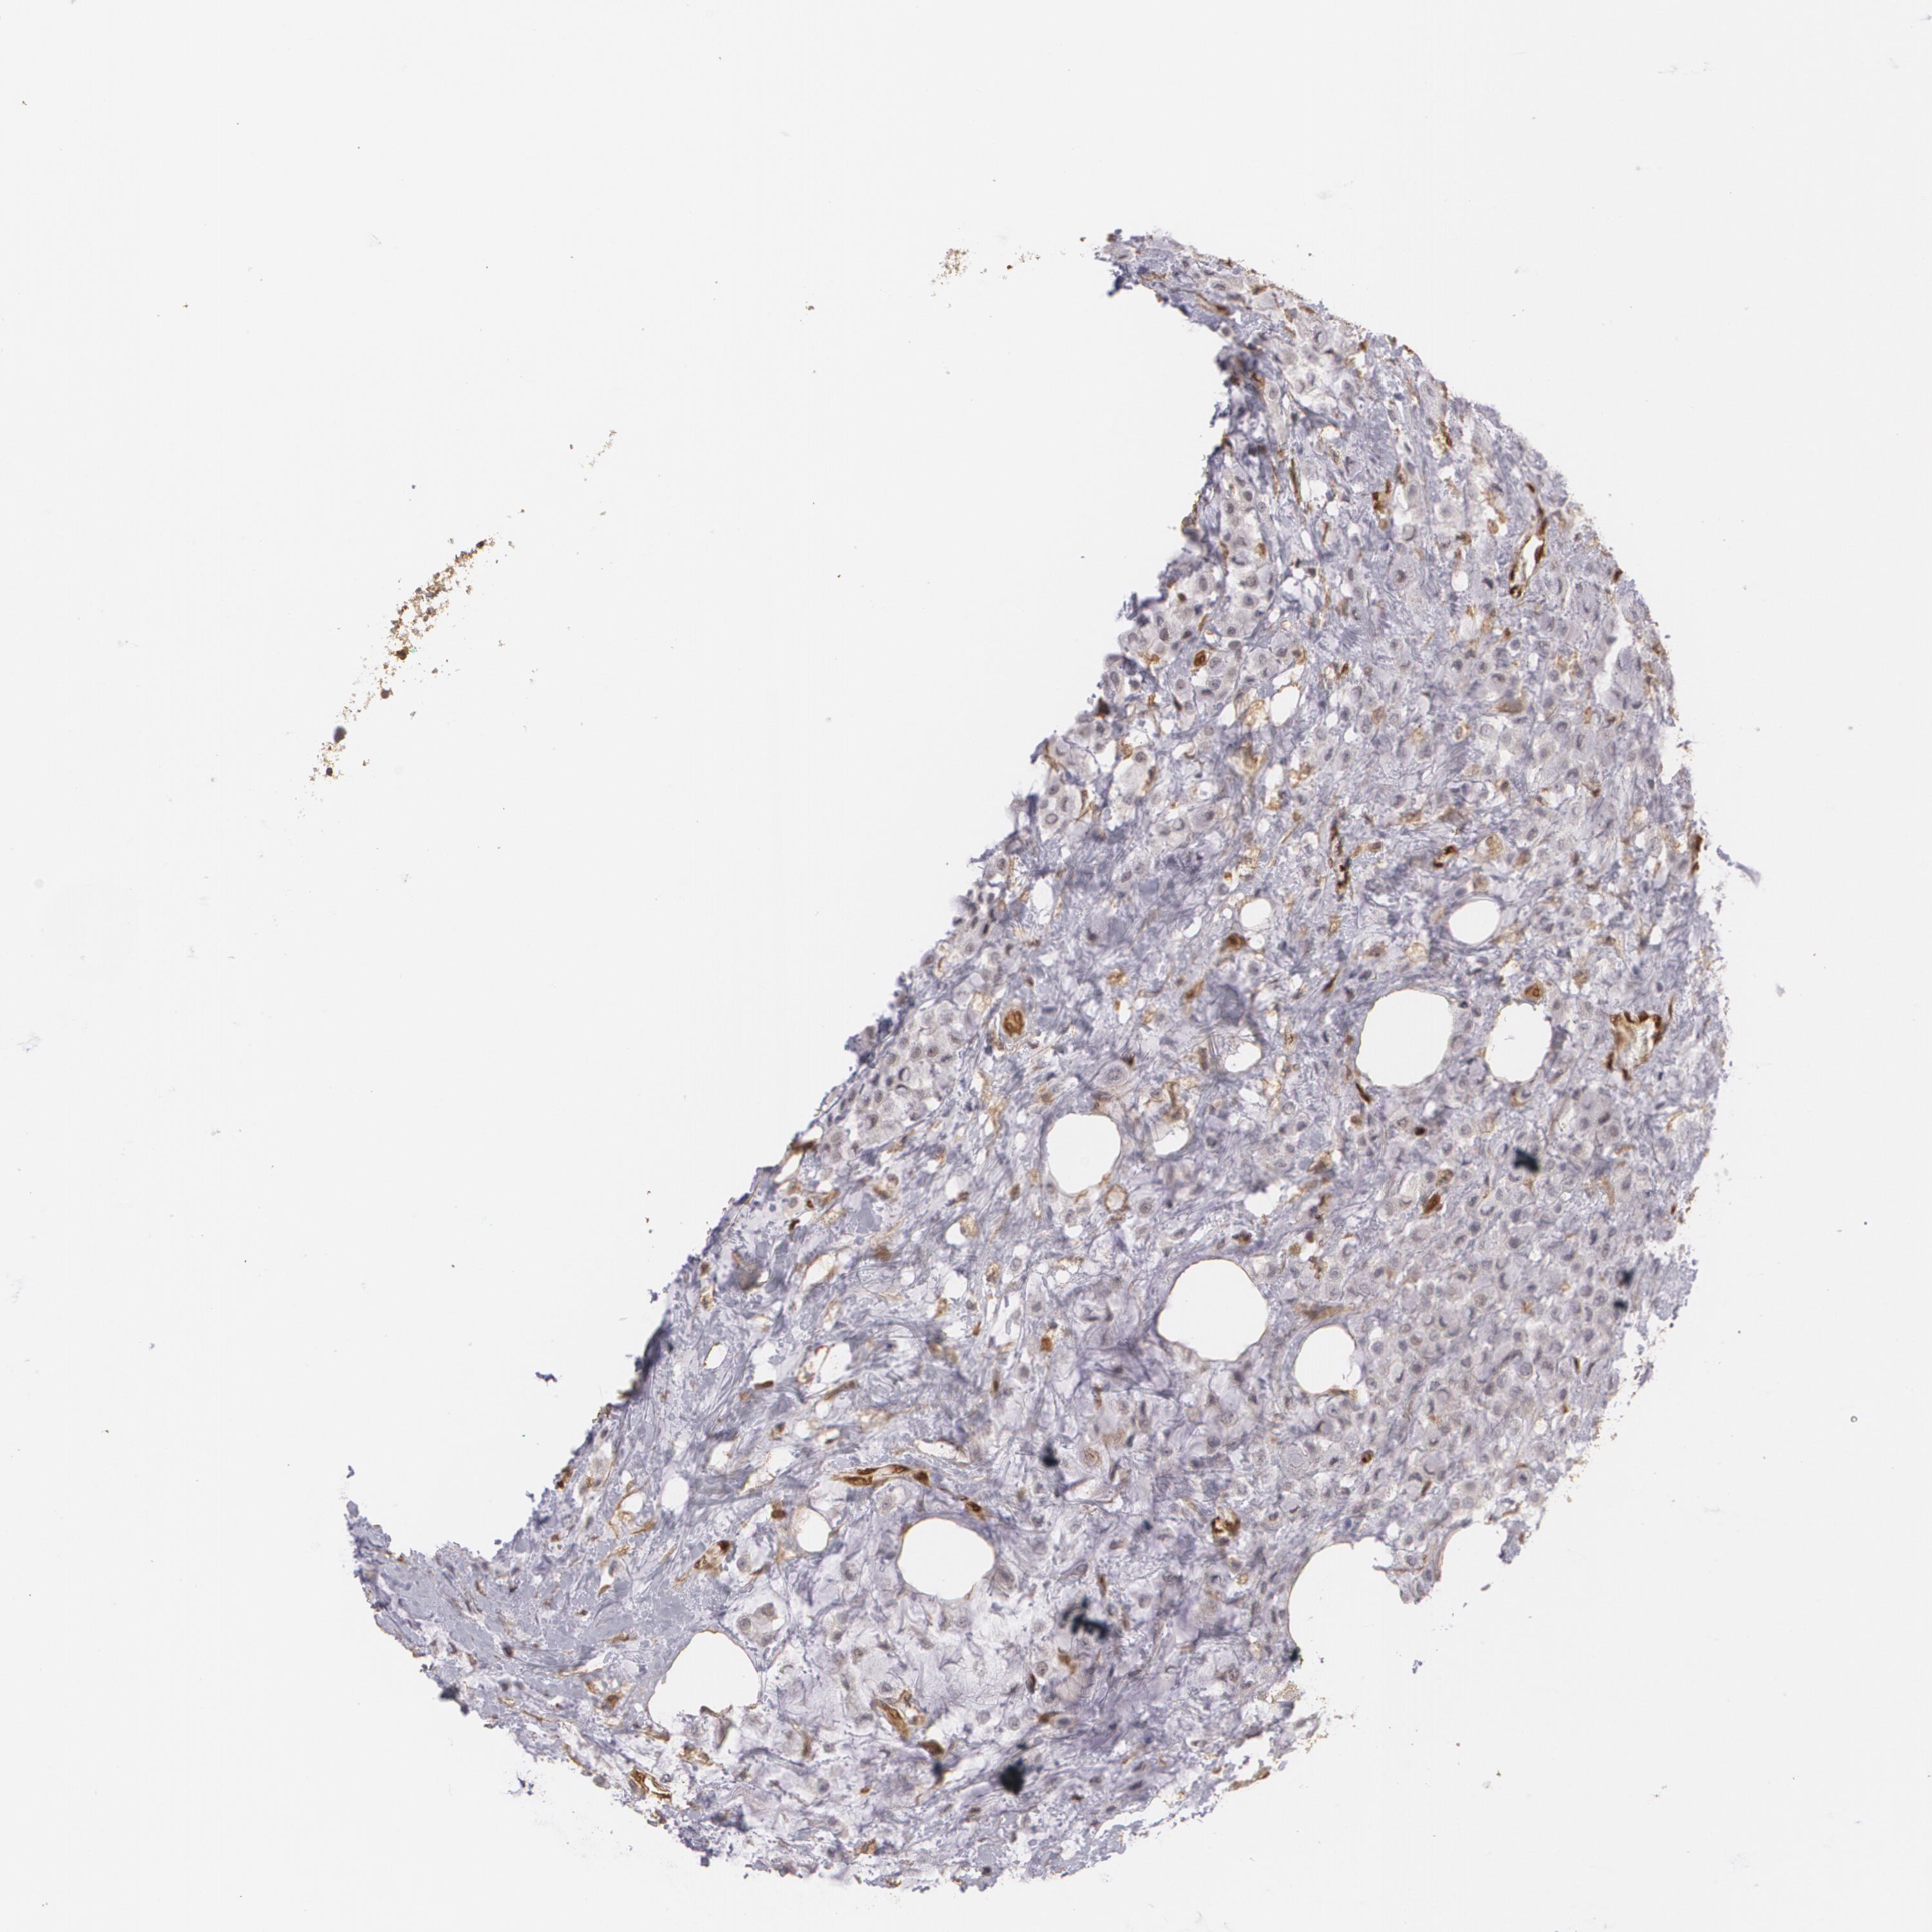

BRCA TCGA BRCA VALIDATION PROTEIN EXPRESSION

ANTIBODIES

AND

VALIDATION